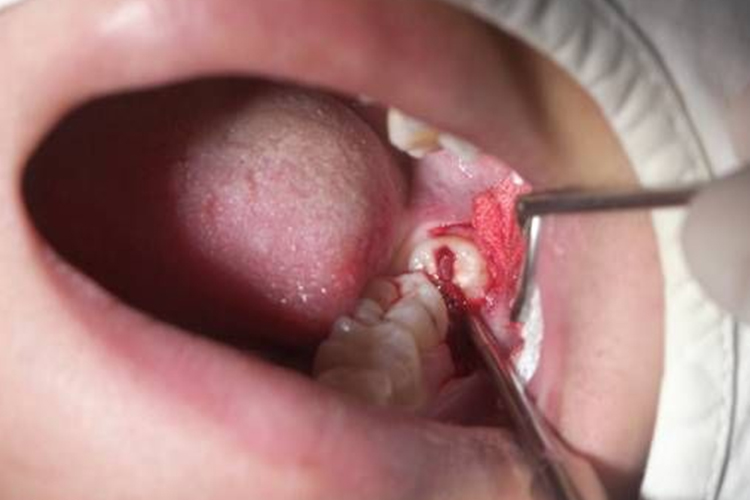

拔除患牙:用牙钳夹紧患牙后,运用摇动、扭转和牵引力拔除患牙。应向阻力较小的方向多用力,防止发生断根或牙槽骨折裂。

拔牙创处理:检查拔除的患牙是否完整,如发现有断根应予拔除。用刮匙清理拔牙创,对过高或过尖的骨峭、牙槽中隔或牙槽骨板用骨凿、咬骨钳、骨锉等进行修整。若术中进行切开﹑翻瓣拔牙或牙龈撕裂者,还需对位缝合,但一般拔智齿患者不需进行缝合。